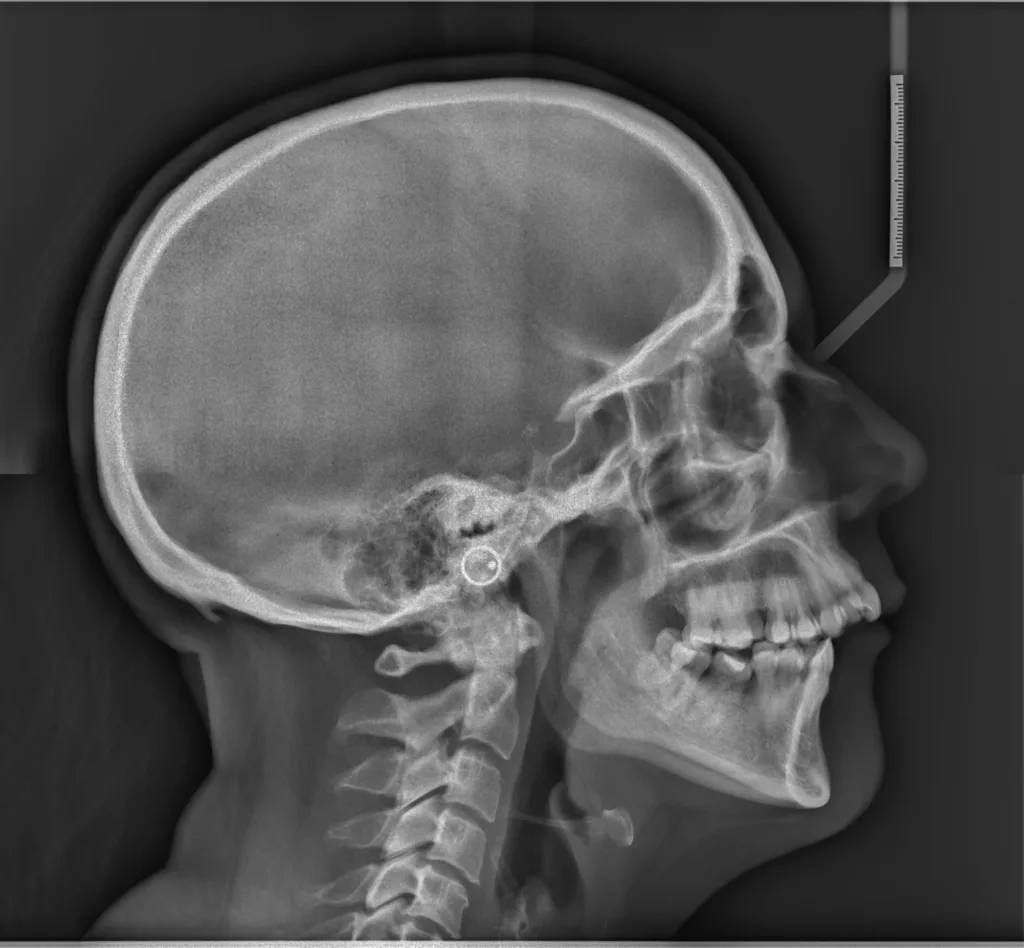

Parmi les examens radiographiques nécessaires, les radiographies de profil et de face correctement orientées et contenant l’ensemble de la tête (sommet du crâne inclus) sont particulièrement importantes. Ces radiographies correctement effectuées permettent d’établir une véritable cartographie du squelette du patient et en conséquence de comprendre sa malformation. Cette analyse cartographique du squelette a pour nom « céphalométrie ». De nombreux types d’analyses céphalométriques existent et sont utilisées selon les pays et universités. Parmi elles, l’analyse céphalométrique architecturale et structurale de Jean Delaire tient une place particulière.

L’Analyse Céphalométrique architecturale et structurale de Jean Delaire

L’analyse céphalométrique architecturale crânio-faciale de Jean Delaire, à la différence des autres méthodes d’analyse qui sont principalement basées sur des moyennes statistiques définissant ce qui est « normal » et ce qui est « anormal » (c’est à dire pathologique) est basée sur la notion d’équilibre ou de déséquilibre architectural du squelette crânio-facial propre à chaque individu en tenant compte des principaux appareils anatomiques à son contact et des principales fonctions qui interfèrent avec lui. « A l’état d’équilibre, tous les éléments de l’extrémité céphalique ; squelette et tissus mous sont et fonctionnent en parfait équilibre mutuel ».

Pour chaque individu, l’analyse architecturale crânio-faciale de Jean Delaire permet de déterminer « l’équilibre » squelettique idéal qui lui est propre c’est-à-dire « sa normalité » et de constater, s’il existe, l’état de «déséquilibre » dans lequel il se trouve, c’est-à-dire l’état « pathologique » dans lequel il se trouve en tenant compte de son âge, de ses antécédents personnels ou familiaux, de son état fonctionnel ou dysfonctionnel, de l’existence d’éventuelles pathologies associées.

Pour chaque patient étudié l’analyse céphalométrique de Jean Delaire permet de :

- Connaître et de quantifier le morphotype qui lui est propre

- Analyser la situation d’équilibre (la normalité) ou de déséquilibre (la situation pathologique) dans laquelle se trouve l’ensemble de son extrémité céphalique ; crâne, massif facial et rachis cervical (analyse architecturale),

- Déterminer la participation respective de chaque élément anatomique dans la malformation ; maxillaire, mandibule, os basal, os alvéolaire, dents (analyse orthognathique et dentaire),

- Evaluer l’anomalie de position de chacune des pièces et unités anatomiques et de connaitre la position qu’elles auraient dû avoir en l’absence de pathologie guidant ainsi au mieux le chirurgien dans son plan de traitement chirurgical (analyse topographique)

L’analyse architecturale est complétée par l’analyse structurale. Pour chaque patient elle consiste à examiner attentivement tous la « structure » de l’extrémité céphalique c’est dire l’anatomie de chacune des pièces squelettiques et des parties molles qui la compose pour mieux comprendre le mécanisme d’installation et d’entretien de la dysmorphose. En association avec l’analyse architecturale elle permet de poser le diagnostic le plus précis afin de choisir le meilleur traitement chirurgical et orthodontique.